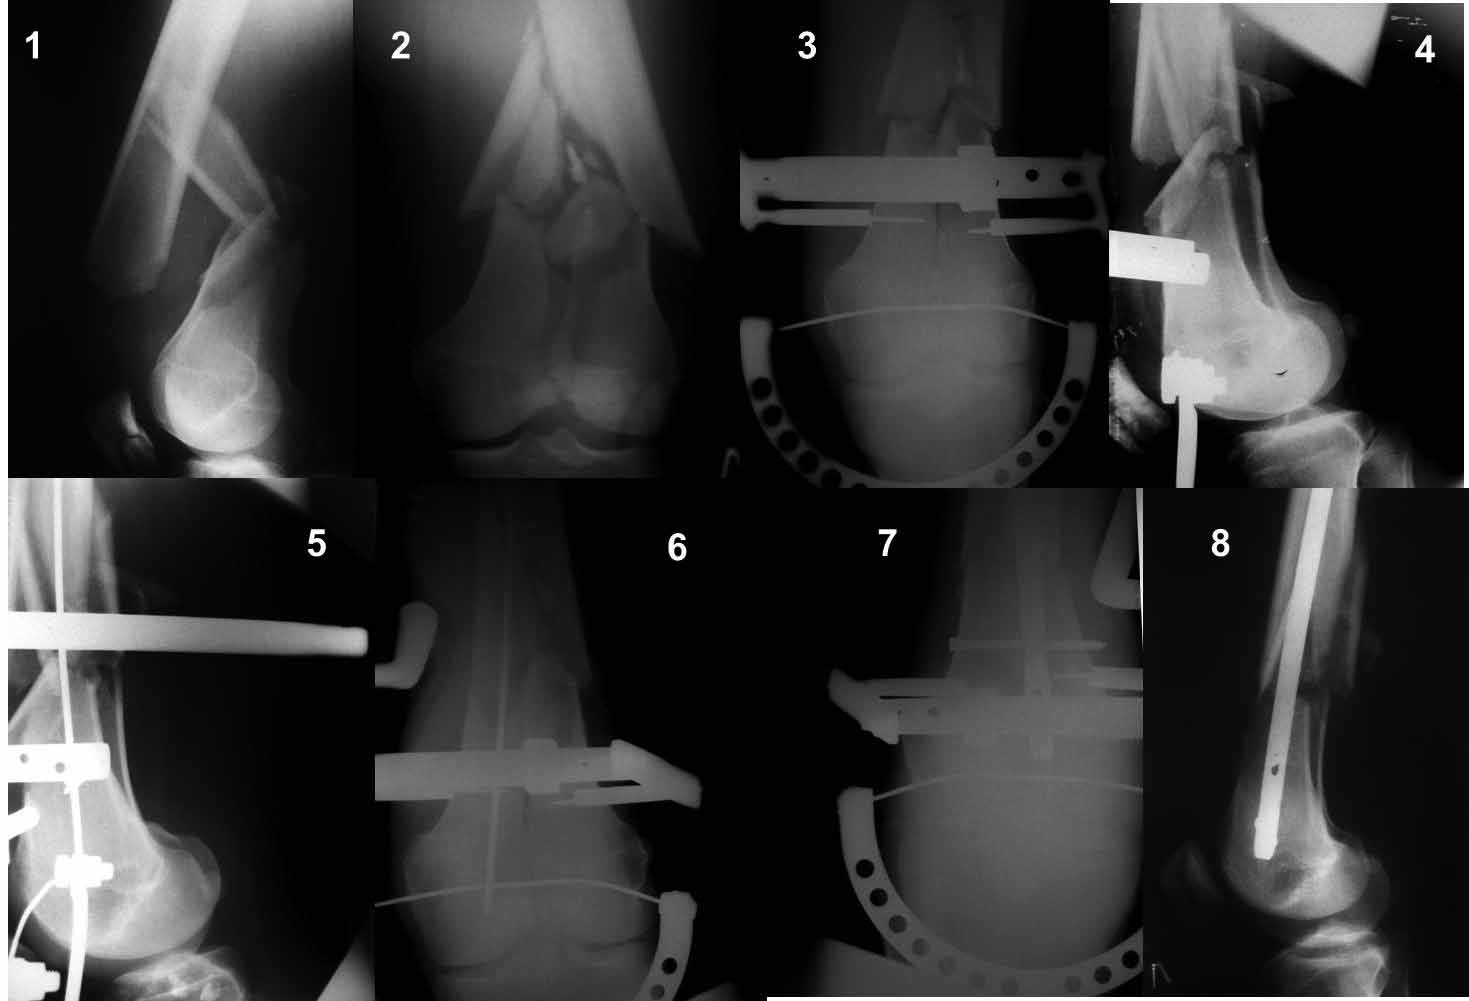

Ну зачем же так. Всё-таки считается "золотым стандартом". Во вложенном файле коллаж из сохранившихся фотографий одной из операций. Всё сделано закрыто и без ЭОПа.

Имя     : dist. femur.jpg